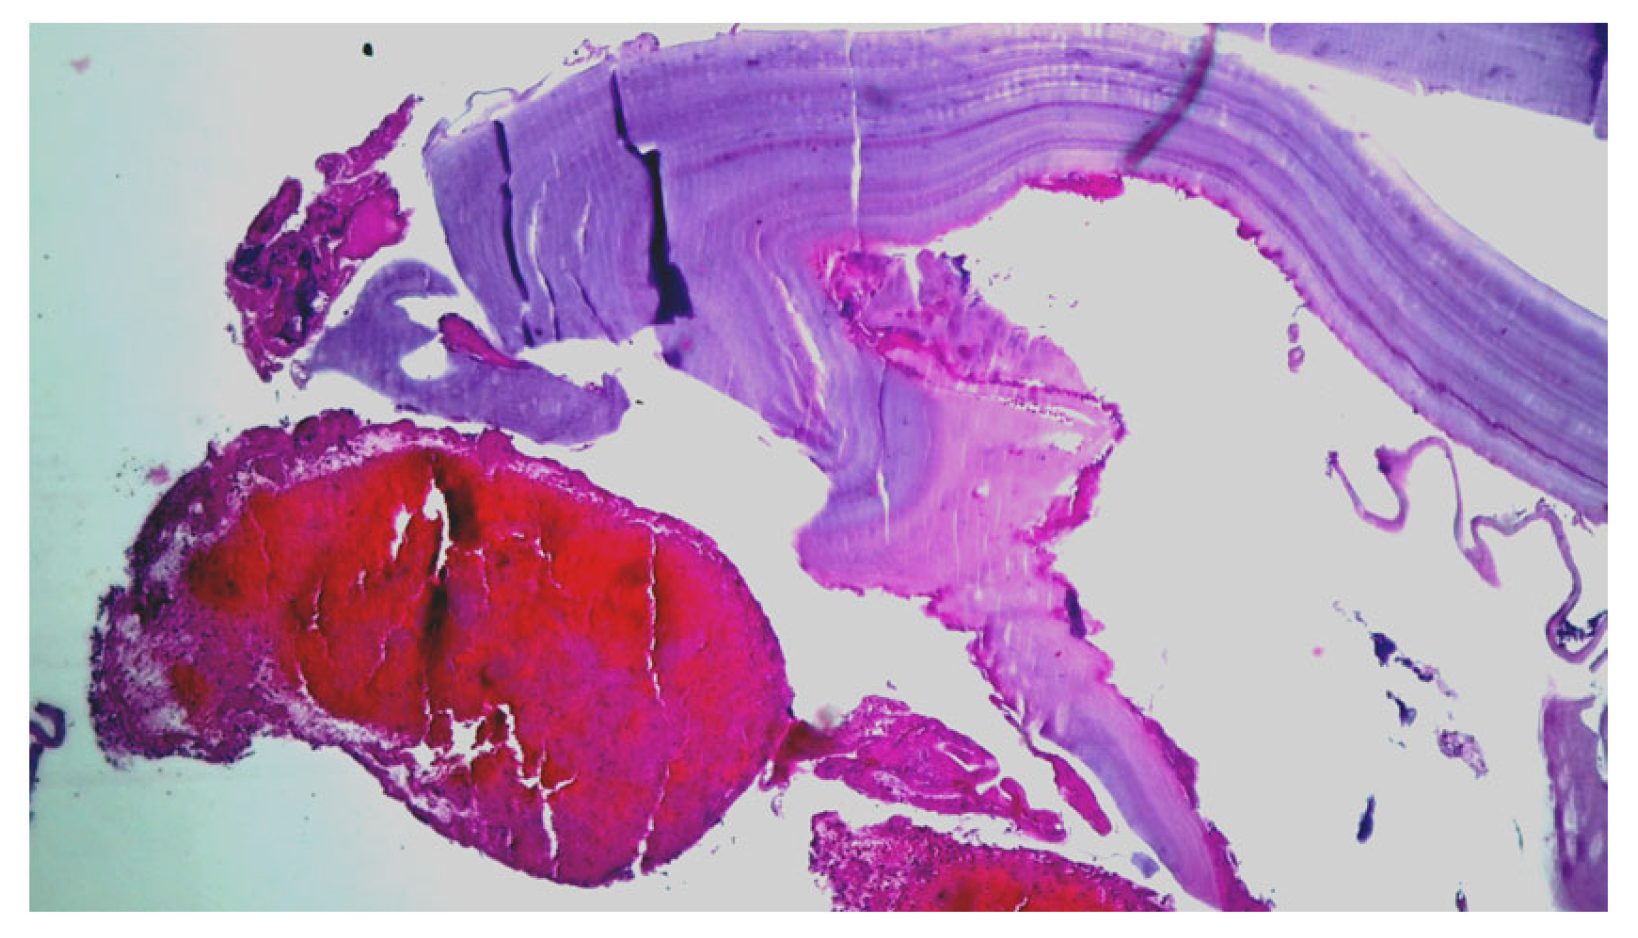

Emergency surgery was performed to treat the acute brachial artery ischemia, as the patient showed early signs of motor deficit. A surgical sample fragment suggesting a ruptured hydatid cyst membrane was histopathologically assessed and confirmed the diagnosis of arterial embolism due to a hydatid cyst membrane fragment. The sample tissue was a fibrino-hematic clot with rich granulocytic inflammatory infiltrates, intense eosinophilia, and included multiple fragments of anhistous membrane (avascular, eosinophilic, retractile, laminated) from the structure of the hydatid cyst. The histopathological aspect was suggestive of a hydatid embolism, seen in Figure 3a–d and Figure 4.

Figure 3.

Histopathological examination of the hydatid cyst membrane collected from the brachial artery: (a) HE × 40: fibrin clot enclosing fragments of the anhistous membrane; (b) HE × 100: anhistous membrane fragment embedded in fibrin-blood clot; (c) HE × 40: anhistous membrane fragment; (d) Histopathological examination HE × 40: anhistous membrane fragment and blood clot.

Figure 4.

Histopathological examination: HE × 40: anhistous membrane fragment with associated dense inflammatory infiltrate.